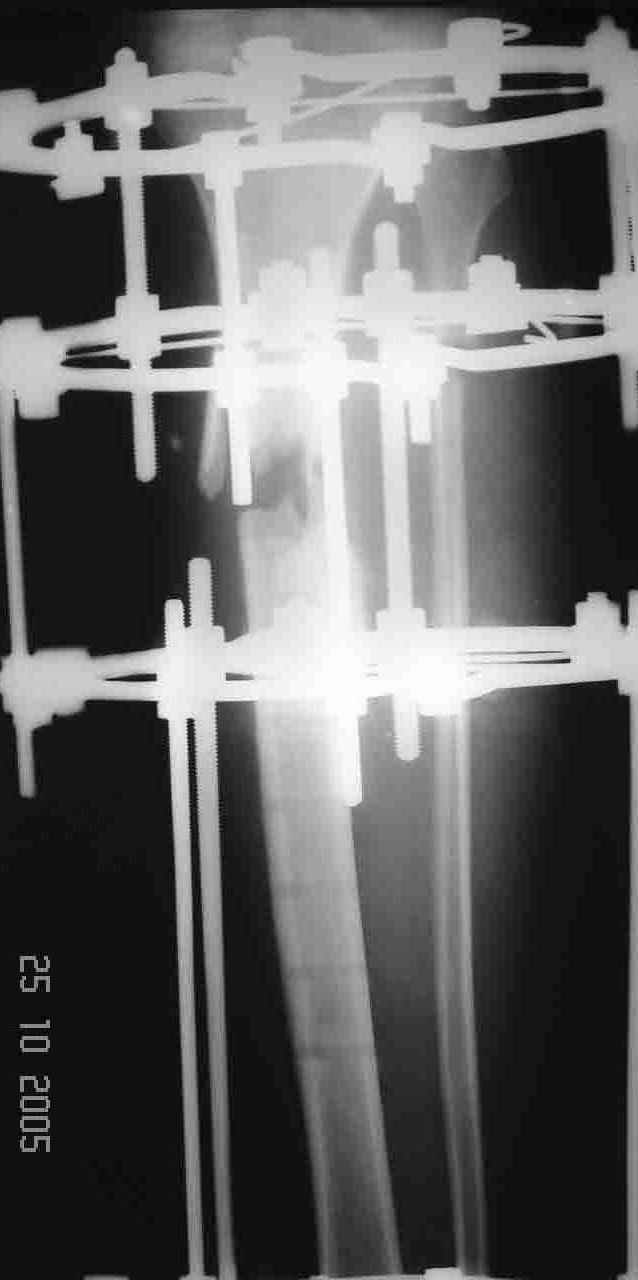

Re: Несращение tibia с LCP

послал Алексей Смирнов 26 Октябрь 2005, 14:17

На операции после удаления пластины вывалился промежуточный свободный фрагмент,оставлять его посчитали нецелесообразным. После его удаления вскрыли костномозговой канал, зашили рану и наложили аппарат. После заживления раны концы отломков сблизили. Возможно, всё это же можно было бы сделать одномоментно и на стержне. Но как то мы не решились забить гвоздь при наличии большой раны и костного дефекта. Сейчас 2 недели после операции, больной ходит при помощи костылей с одинаковой нагрузкой на обе ноги. Укорочение в итоге 1,5 см. Обязуюсь показать снимки через пару месяцев.